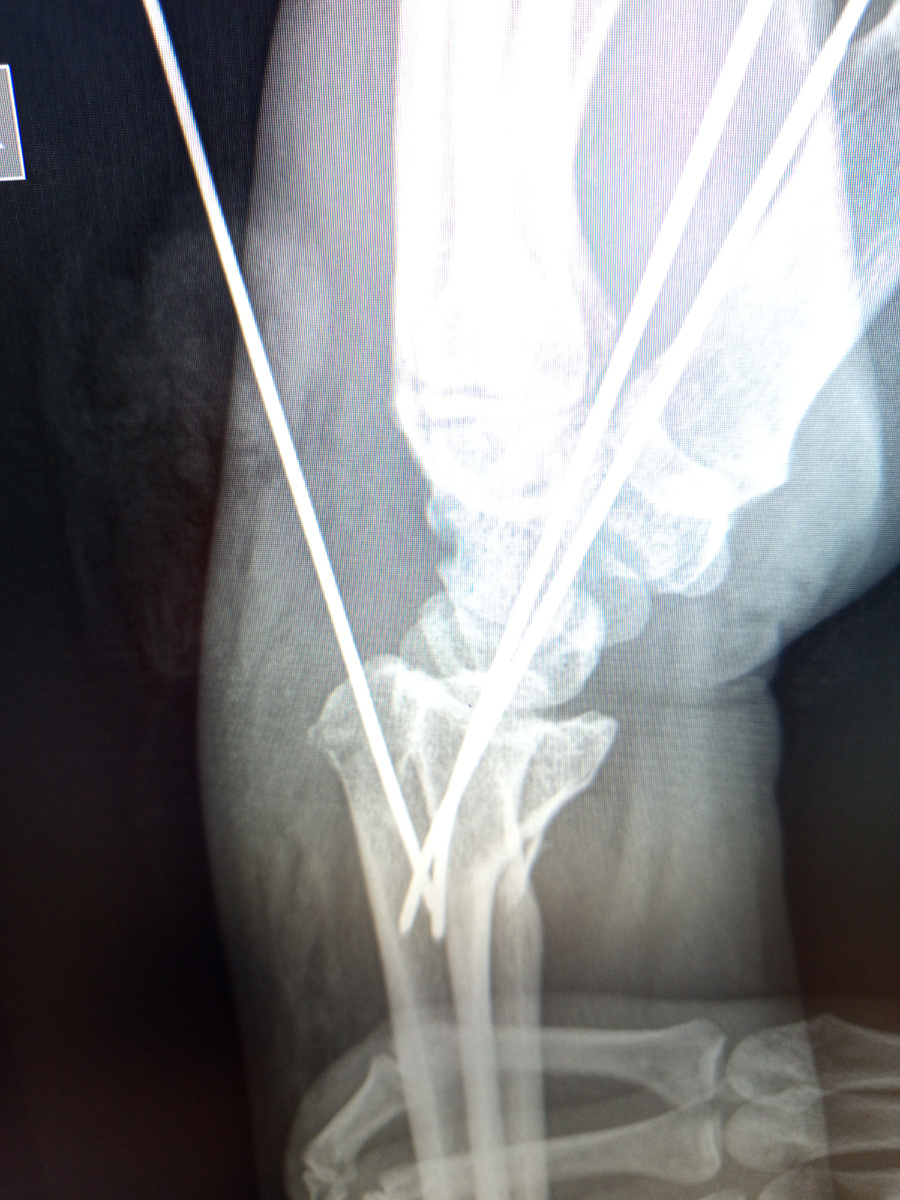

Уже спицы поставили , лоб заклеен. Назначили левый лучезапястный , череп и правую стопу.

Не , это все переделывать надо, госпитализировали женщину, она , кстати еще и большой палец на стопе сломала.